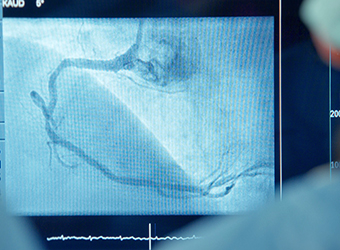

Hochkomplexe Herz-Gefäß-Medizin

Die komplexeste Herz-Gefäß-Medizin der Bochumer Region findet an unserem Standort statt.

Wir behandeln schwerste kardiale und kardiovaskuläre Krankheitsbilder mit modernsten diagnostischen und therapeutischen Verfahren – präzise, schnell und evidenzbasiert.

Zum Leistungsspektrum gehören unter anderem:

- extrakorporale Herz-Kreislauf-Unterstützung (ECMO)

- mechanische Kreislaufunterstützungssysteme (z. B. Impella)

- invasive und nichtinvasive Hochleistungsdiagnostik